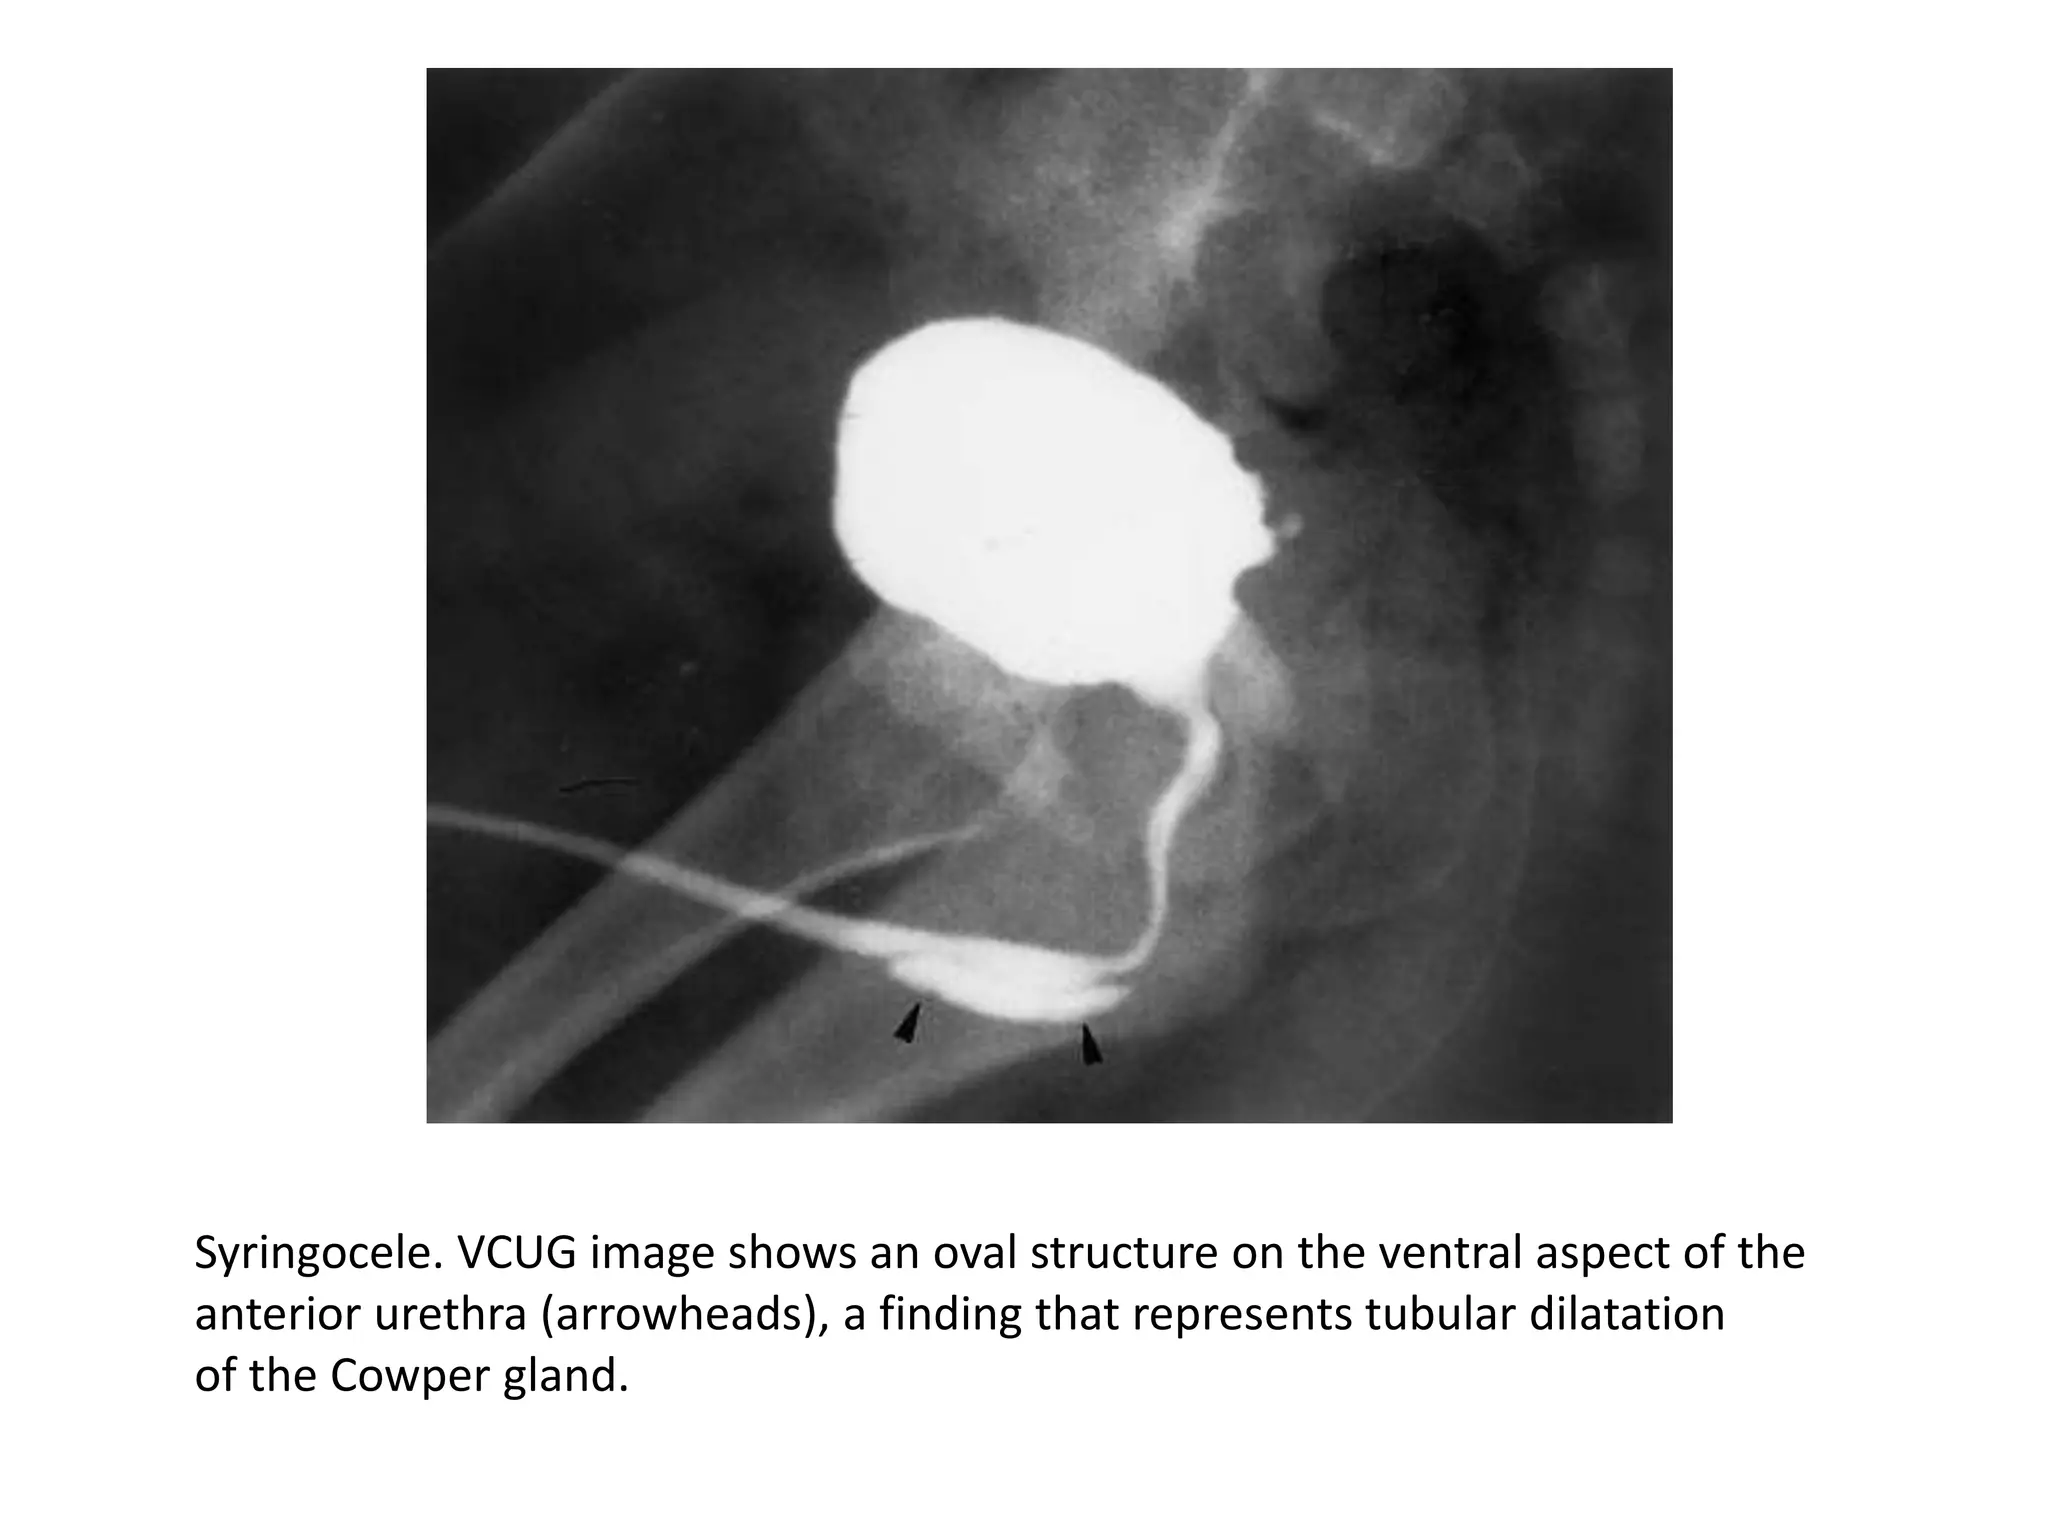

Syringocele. VCUG image shows an oval structure on the ventral aspect of the

anterior urethra (arrowheads), a finding that represents tubular dilatation

of the Cowper gland.

• Cowper’s syringocele, a rare anomaly, occurs when

there is dilatation of the main draining duct.

• During VCUG, the

main duct and

Cowper’s glands can

fill with contrast

material and appear

as a tubular channel

paralleling the ventral

aspect of the

undersurface of the

bulbous membranous

urethra and ending at

the urogenital

diaphragm.

• This finding is usually

of no clinical

significance.